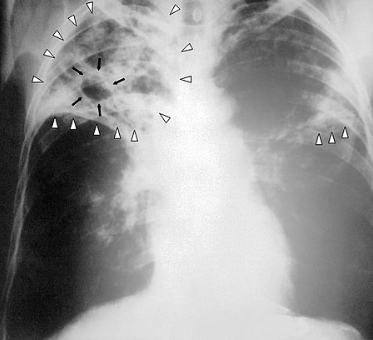

• 흉부 X선 검사: 결핵이 폐에 영향을 미치는 경우, 흉부 X선 검사를 통해 폐의 이상을 확인할 수 있습니다. 이 검사는 결핵의 초기 징후를 발견하는 데 유용합니다.